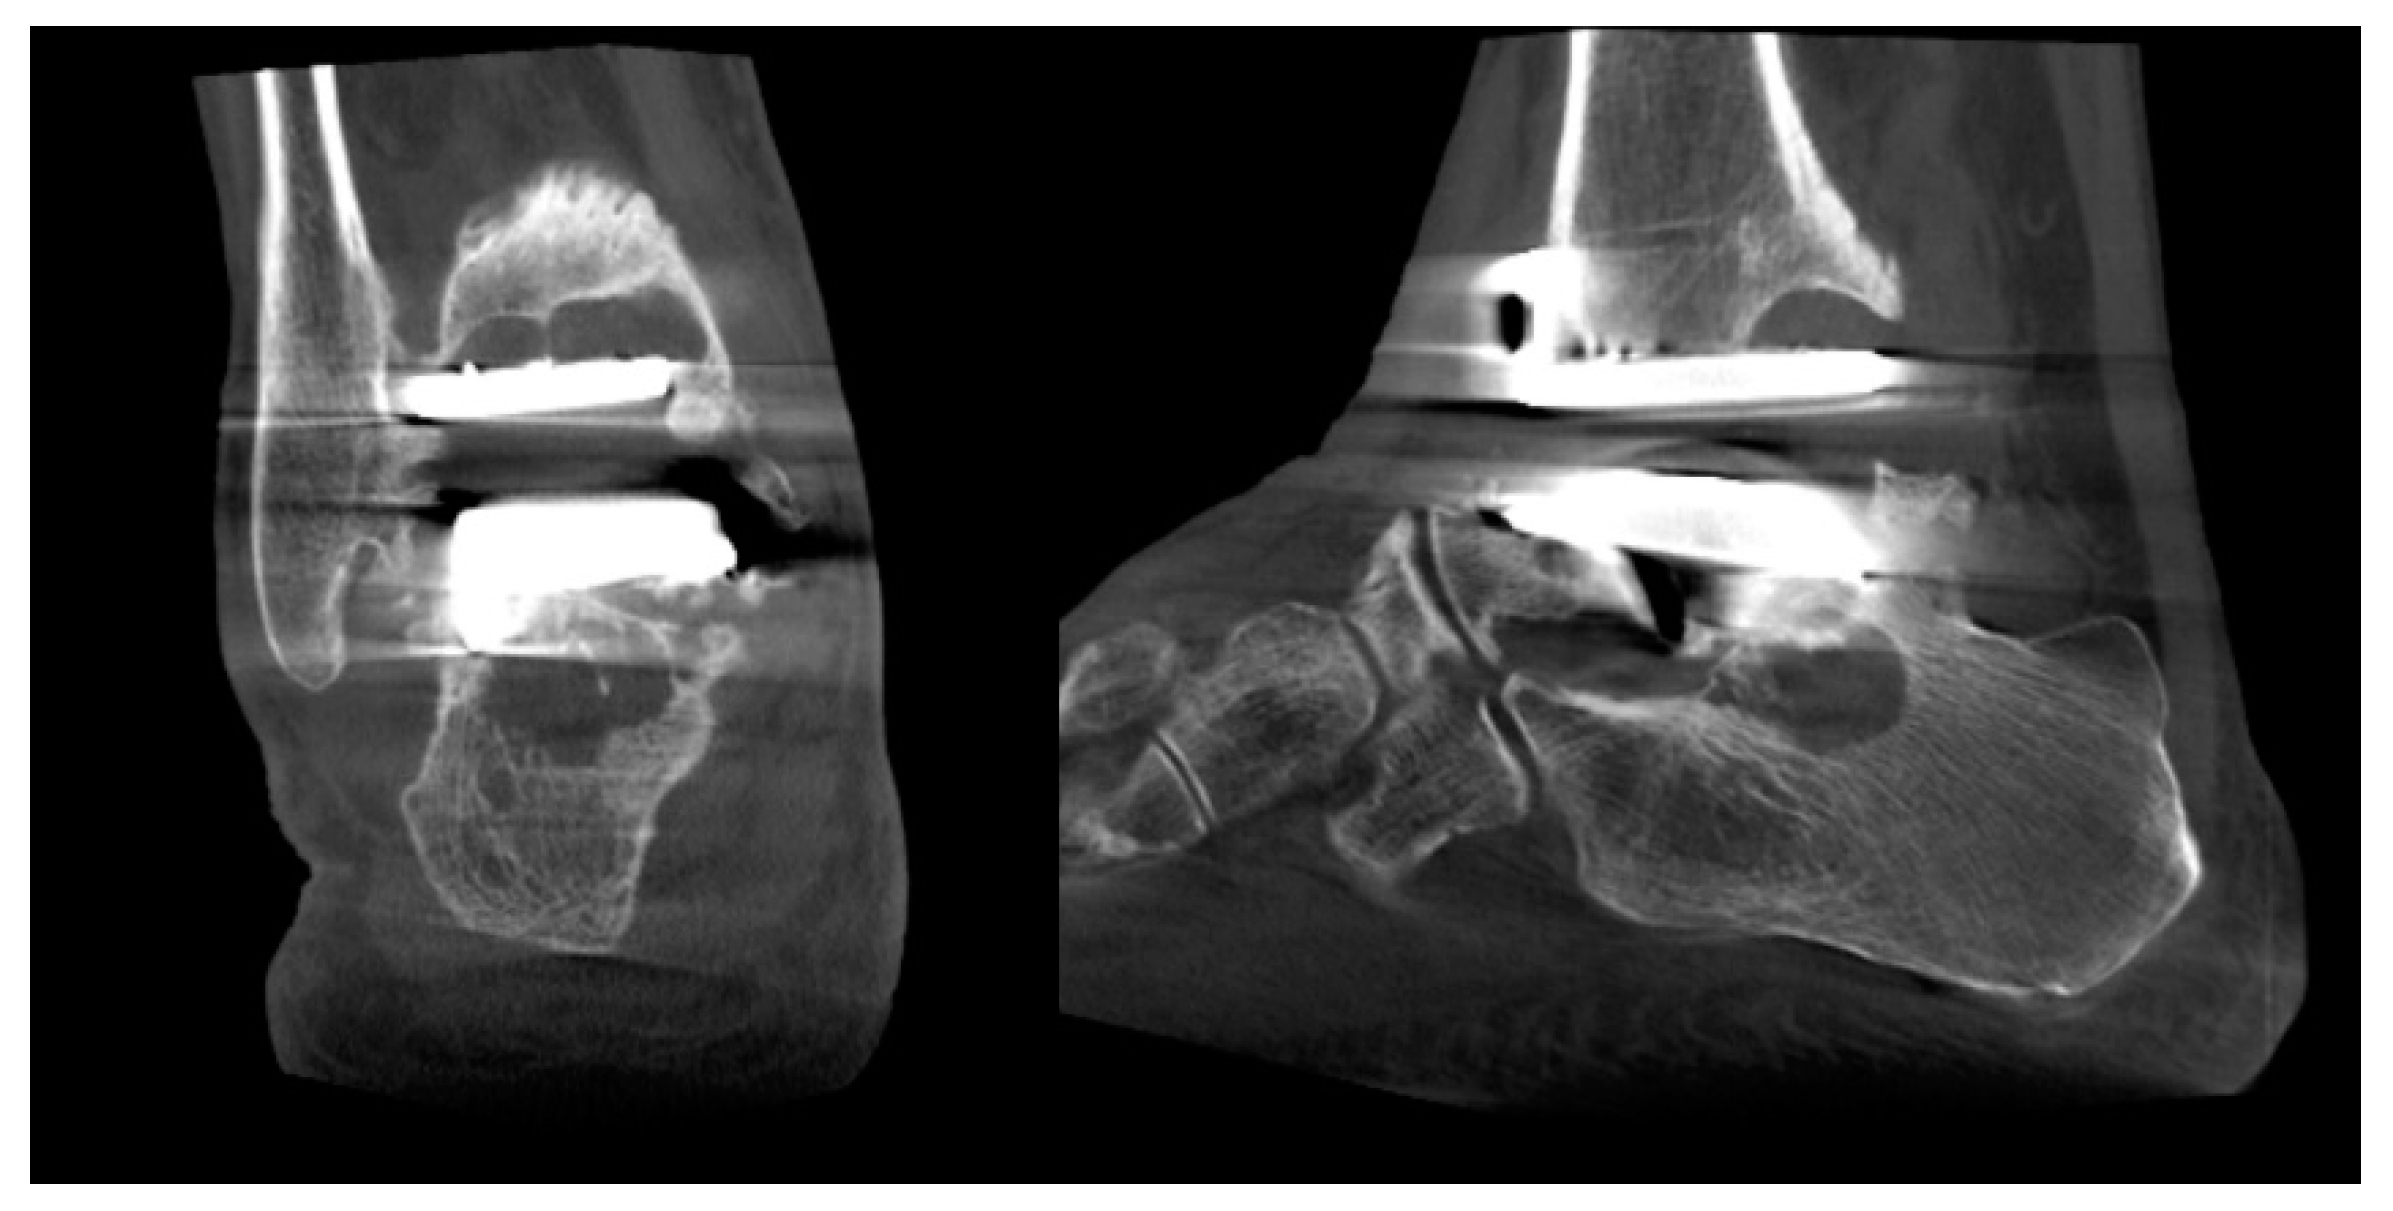

Ankle Replacement Surgery

- Lintz, F.; Mast, J.; Bernasconi, A.; Mehdi, N.; de Cesar Netto, C.; Fernando, C.; Buedts, K. 3D, Weightbearing Topographical Study of Periprosthetic Cysts and Alignment in Total Ankle Replacement. Foot Ankle Int. 2020, 41, 1–9. [Google Scholar] [CrossRef] [PubMed]